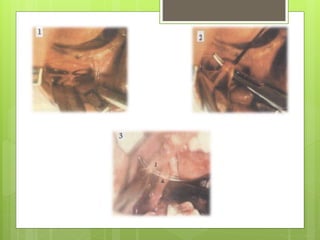

OPEN PROCEDURES ( INTRACRANIAL PROCEDURES):

(A) Microvascular decompression of the trigeminal nerve

sensory root:

Procedure popularized in 1967 – 1976 by Jannetta.

Most commonly performed intra cranial open

procedure.

The root is examined under

the microscope

A compressing branch of

the superior cerebellar

artery will be seen medial to

the nerve at the root entry

zone.

Incision is made over the mastoid area

Then the trigeminal nerve is

freed from the compressing

/ pulsating artery.

After freeing the nerve, the

nerve is separated from the

artery by placing a piece of

Teflon between them.

Non absorbable insulating sponge

may also be placed.

OPEN PROCEDURES (INTRACRANIAL PROCEDURES): (A) Microvascular decompression of the trigeminal nerve sensory root: Procedure popularized in 1967 – 1976 by Jannetta. Most commonly performed intra cranial open procedure. The root is examined under the microscope

• 68.

A compressing branchof the superior cerebellar artery will be seen medial to the nerve at the root entry zone. Incision is made over the mastoid area

• 69.

Then the trigeminalnerve is freed from the compressing / pulsating artery. After freeing the nerve, the nerve is separated from the artery by placing a piece of Teflon between them.

• 70.

Non absorbable insulatingsponge may also be placed.